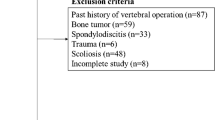

We prospectively studied the hips of 21 children being evaluated with MRI for probable necrosis of the femoral head showing epiphyseal abnormalities on plain radiography. We excluded patients with conditions resulting in marrow abnormality, such as sickle cell disease or leukemia, and patients receiving medications predisposing to avascular necrosis of the femoral head, such as steroids and chemotherapeutic drugs. Of these, 17 children had a diagnosis of LCP by typical radiographic findings and/or perfusion abnormalities in bone scintigraphy. We excluded the remaining four children, two of whom had epiphyseal dysplasia and two with what we interpreted as a normal radiographic variation. The mean age of the 17 patients with LCP was 6 years (range, 2–12 years). Fifteen patients were boys and only one hip was involved in each child. We established the lack of involvement of the contralateral femoral head using normal serial radiographs and a normal MRI examination, allowing us to use the contralateral hip as a control. The interval between onset of symptoms and imaging ranged from 1 day to 5.8 years (mean, 47 weeks; median, 16.3 weeks).